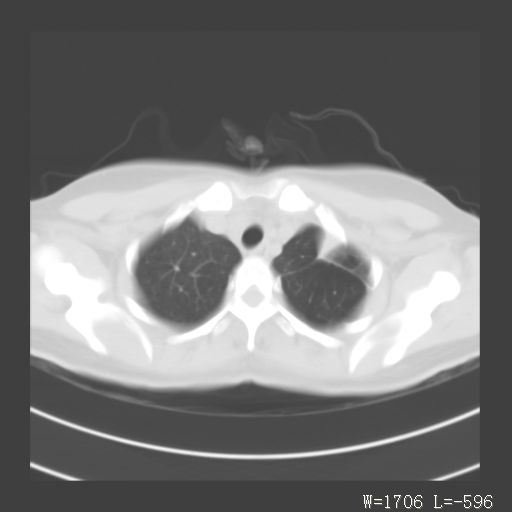

1)考虑左肺上叶肺脓肿,节段性肺不张。2)永存左上腔静脉。

1)考虑左肺上叶节段性肺不张。原因?2)永存左上腔静脉。

支持肺脓肿;还是双上腔静脉确切些吧,回流至冠状窦或右心房。

考虑左肺上叶胸腺瘤可能性大。肺不张/永存左上腔静脉

1、胸骨后偏左侧囊实性病灶,考虑胸腺瘤可能性大。2、永存左上腔静脉。